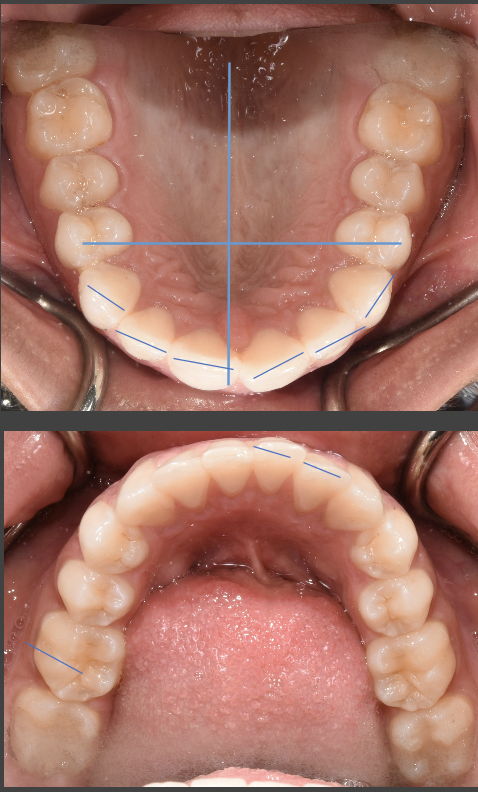

Almost-brodie bite with SFOT. Looking for provider recommendations

I went to my original orthodontist really wanting a wider smile and a fix to my overbite {content removed} sleep apnea. He proposed removing two premolars in order to prepare for double jaw surgery. I had the two lower premolars removed in addition...

My right side molars on top and bottom are lower than the left side. Is this fixable?

My right side molars on both top and bottom are lower than the left side which or placed correctly. I’ve been in braces for over two years now and have not seen any correction in this, despite it being my main concern. My right side profile looks...